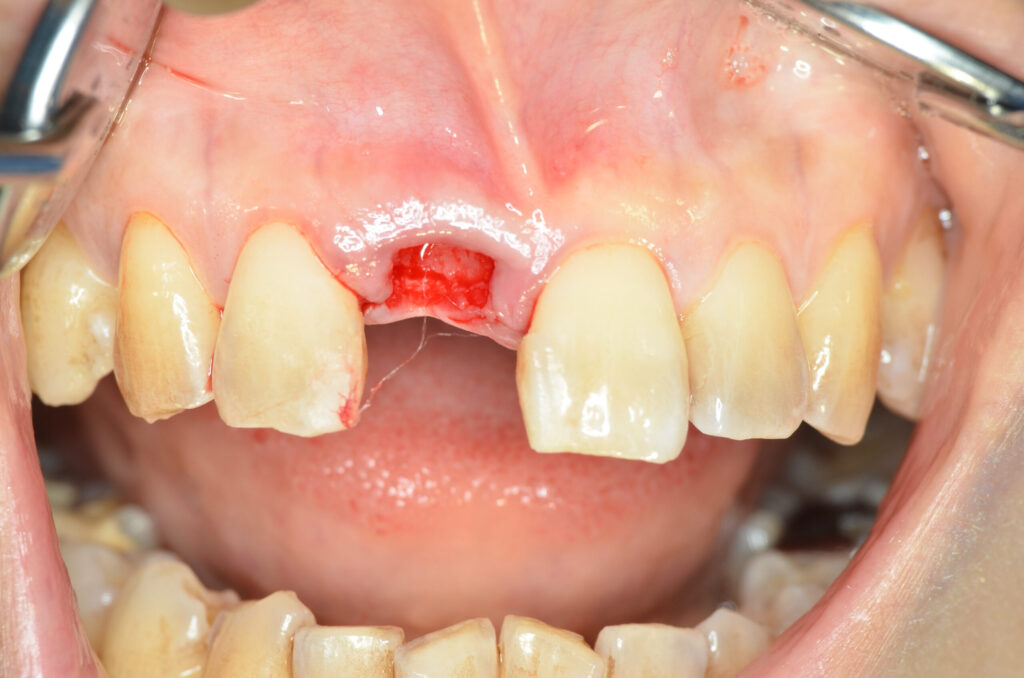

Before

治療内容

インプラント1本・骨造成・歯肉移植

治療のリスク

外科手術が必要になるため、患者様に体力的な負担がかかる。